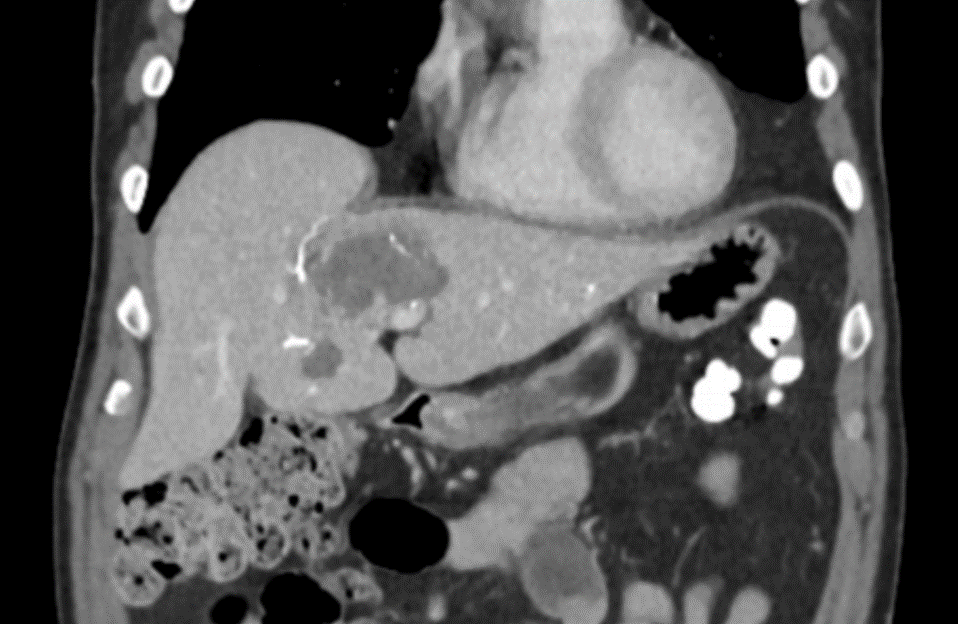

LC Bead LUMI: NET; 48h FU; MDCT Coronal Plane

NET; 48h FU; MDCT Coronal Plane

After LUMI embolization — with lasting radiopacity, LC Bead LUMI™ continues to be visible in follow-up scans1.

ACC: adenoid cystic carcinoma; CBCT MIP: Cone-beam computed tomography maximum intensity projection; DSA: digital subtraction angiography; HCC: hepatocellular carcinoma; MDCT: multidetector computed tomography; NET: neuroendocrine tumor. Images courtesy of NIH with permission*.

LC Bead LUMI is easily visualized with CT. Early experience images from various different tumor types, show discrete embolized vessels where LC Bead LUMI is present with no significant streak artifacts nor masking of adjacent tissue unlike commonly seen following lipiodol-containing treatments. If contrast enhanced CT images are desired, obtaining a non-contrast image may be helpful to discriminate LC Bead LUMI from contrast enhancement.